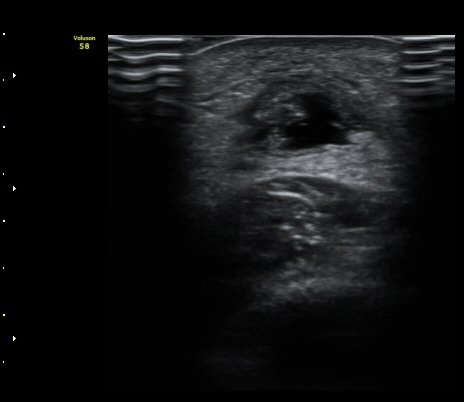

ÃÊÀ½ÆÄ °Ë»ç